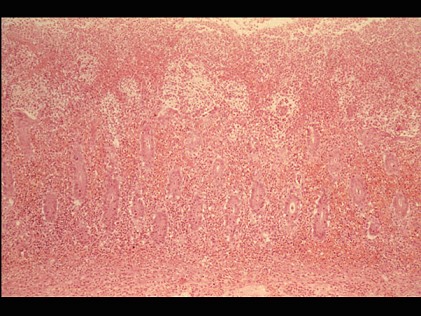

根据图,关于菌痢的病理改变正确的是()

A.黏膜充血、水肿、中性粒细胞和巨噬细胞浸润

B.粘膜下层、肌层、浆膜层有明显的炎症反应

C.假膜主要为纤维素、坏死的肠粘膜、细菌、嗜中性粒细胞及红细胞等,部分有脱落

D.整个肠粘膜有假膜覆盖,粘膜上皮及腺体大片消失

E.大约一周左右,假膜开始脱落,形成大小不等,形状不一的“地图状”溃疡如图